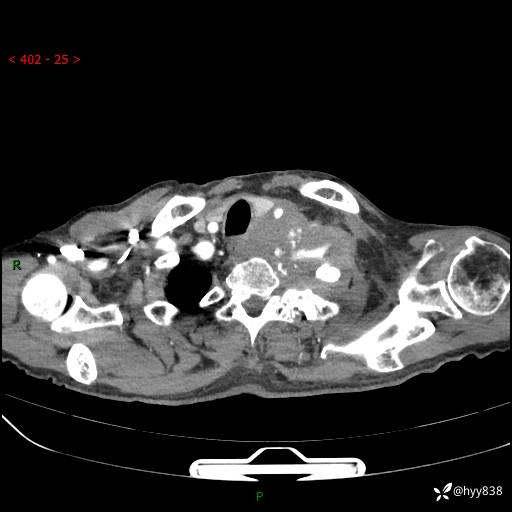

老年男性,气促5月,胸背痛2月。发现肺尖较大肿块,摧枯拉朽之势---结果公布~

现病史:患者于5月前饮酒后突发静息状态下气促不适,无胸闷、胸痛、发热、咳嗽、咳痰等不适,于当地第五人民医院及我院就诊,输液治疗后(具体不详)后气促稍缓解,遂出院后自行口服中草药治疗。近2月出现胸背痛,伴左上肢疼痛、乏力、感觉异常,稍有咳嗽、咳痰,咳黄痰、痰液粘稠,无咳血。为进一步诊治来我院。

胸部CT增强扫描(外院平扫)